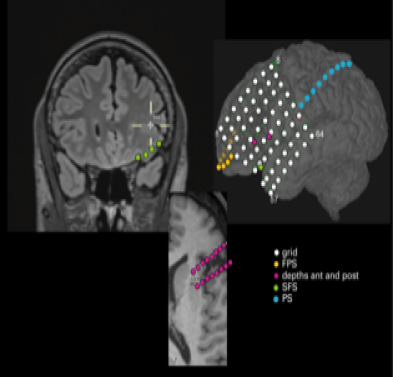

Refer to caption

(a) Electrode Placement

Figure 2: Patient 1’s directional brain networks identified by the new MARSS. (a) The intracranial EEG electrode placement on the left hemisphere of Patient 1. (b)-(f) The identified directional brain networks from 300 seconds before to 225 seconds after seizure onset. The diamond at electrode G37 is the SOZ identified by expert interpretation of EEG data. Nodes in light blue are the regions that did not belong to any clusters. Nodes in the same other colors (either dark blue, green, pink, red, purple, brown or yellow) denote different identified clusters of regions. All nodes in red color belong to the SOZ cluster. Grey arrows indicate the identified directional connections between regions. Anterioinferior electrodes preceded by an “X” were resected in a previous epilepsy surgery. The evolution of the brain network from 300 seconds before to 300 seconds after seizure onset is shown as a video in the supplementary files.